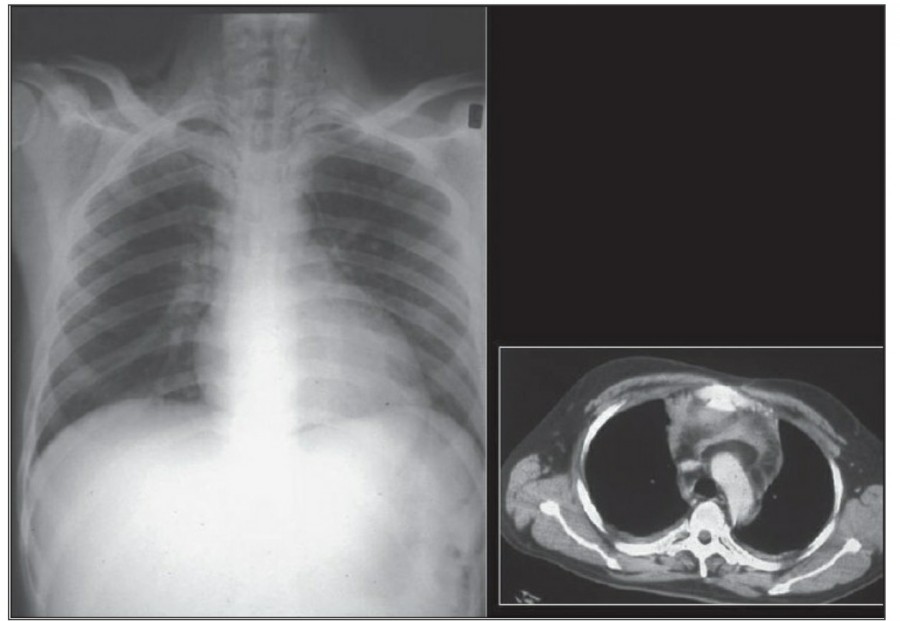

Pneumothorax

공기는 nondependent position으로 위치하므로, X ray상에서는 환자 자세에 따라 다르게 나타난다. Erect position에서 공기는 lung의 apicolateral surface에 위치하고 얇고 하얀 pleural line이 나타나며 그 뒤로 lung marking이 보이지 않는다.

하지만 pleural line 뒤로 lung marking이 존재한다고 해서 pneumothorax를 배제할 수 없다. Pneumothorax의 진단은 특히 parenchymal disease가 있을 때 진단하기 힘든데, 이는 compliance의 변화 때문에 collapse가 잘 안 되기 때문이다. Skin fold가 pneumothorax와 비슷하게 보이기도 한다.

중환자에서 pneumothorax의 진단은 종종 supine radiograph에서 내릴 수 있다. Supine position에서 공기는 anteromedial 방향으로 모이게 되는데, apical air collection이 있을 경우 large pneumothorax가 있음을 시사한다. 공기는 lung과 diaphragm 사이의 subpulmonic location에 trap 되어 있을 수도 있다. 공기가 costophrenic sulcus로 anterolateral extension 될 경우, 이 costophrenic sulcus의 radiolucency를 증가시키는데, 이를 deep sulcus sign이라고 한다. Subpulmonic pneumothorax의 다른 특징으로 diaphragm의 superior surface와 IVC 윗부분이 뚜렷하게 보일 수 있다.

중환자에서 tension pneumothorax의 진단은 매우 힘들다. ARDS와 같은 lung의 병리적인 기전이 lung compliance를 감소시킴으로써 total lumg collapse를 막는다. 또한 tension pneumothorax의 특징인 mediastinal shift가 PEEP으로 인해 나타나지 않을 수 있다. Chest X ray 상에서 tension pneumothorax는 hemidiaphragm의 depression이나 heart border, SVC, IVC의 이동으로 나타날 수 있다.